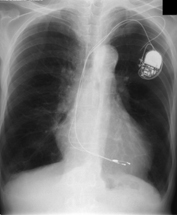

- Age/Sex: 82M

- Chief Complaint: 側傫偲側偔懱偑偩傞偄

- Clinical Course

- 15擭慜 complete AV block偱pacemaker怉偊崬傒

- 嶐擭6寧 COPD偵懳偟偰嵼戭巁慺椕朄

- 嶐擭7寧 寫懹姶弌尰

- 嶐擭8寧 撪壢傊擖堾

- 峛忬態惛嵏偺偨傔I-123峛忬態僔儞僠僌儔僼傿傪梊掕偟偰偄偨偑姵幰偺帠忣偵傛傝戅堾偡傞偙偲偲側偭偨丅

- 戅堾慜偵99mTcO4偵曄峏偟偰峛忬態僔儞僠僌儔僼傿傪巤峴偟偨丅

- Lab. data

- TP:7.8g/dl, T-Bil:1.00mg/dl, ALP:329 IU/L, LAP:66 IU/L,

兞-GTP:114 IU/L, CHE:94IU/L, AST:77.4 IU/L, ALT:40 IU/L,

LDH:140.8 IU/L

- CPK:911IU/L, CPKMB:25.8IU/L

- WBC:3200/兪L, RBC:369枩/兪L, Hb:12.0g/dl, Hct 37.4%, Plt

14.9枩/兪L, CRP 0.1mg/dl

- TSH: 179.76兪U/ml, FT3 0.77pg/ml, FT4 0.66ng/dl,

microsome test 409,600, Anti-TPO Ab >50, Anti-Tg Ab

>100

- Images

- Tc-99m scan: uptake 6.8%

- neck CT